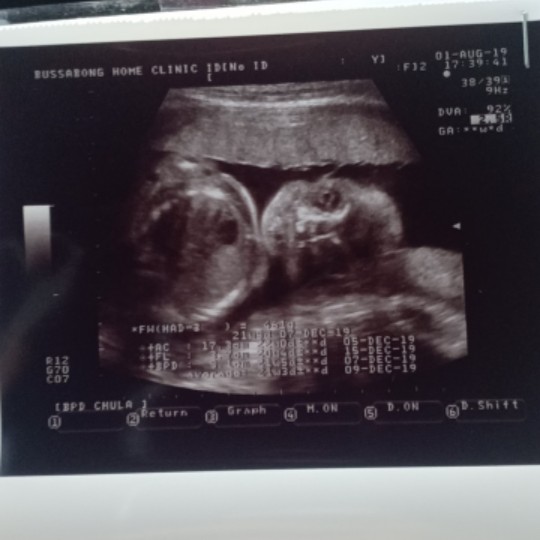

กำหนด25ธันวาภาพซาวตอน20wได้ลูกชาย ตอนนี้23Wแล้วมีใครมองรูปน้องเหมือนแม่บ้านนี้บ้างเอ่ย เห็นตรงกับแม่รึป่าว

23w ลูกชายเหมือนกันค่ะ

23วีคลูกชายเมือกันค่ะ